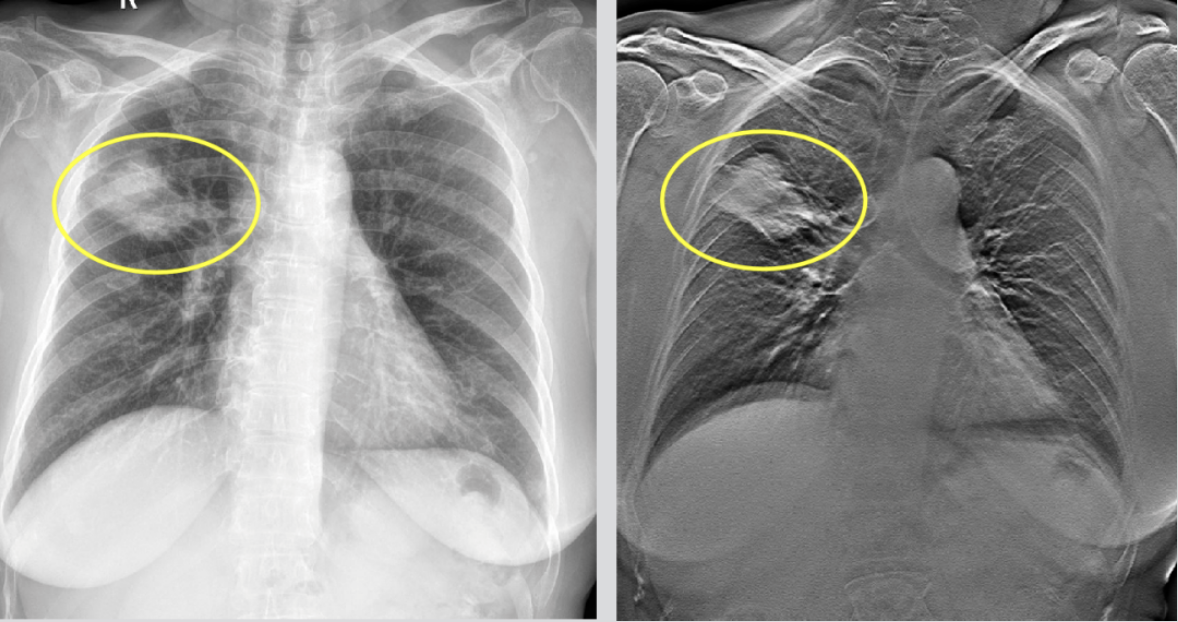

常规DR拍摄

由于二维图像组织重叠和遮挡

对诸多病灶边缘特征及内部结构

无法显示或显示不清晰

导致胸部病灶的漏诊率接近30%

TOMO断层融合技术

能提供冠状面断层图像

解决常规平片因重叠结构

而无法清晰分辨的部分

尤其是纵隔、心影、横隔及肋骨重叠区

结构显示更加清楚

精准提示胸部病变部位

让诊断更精准